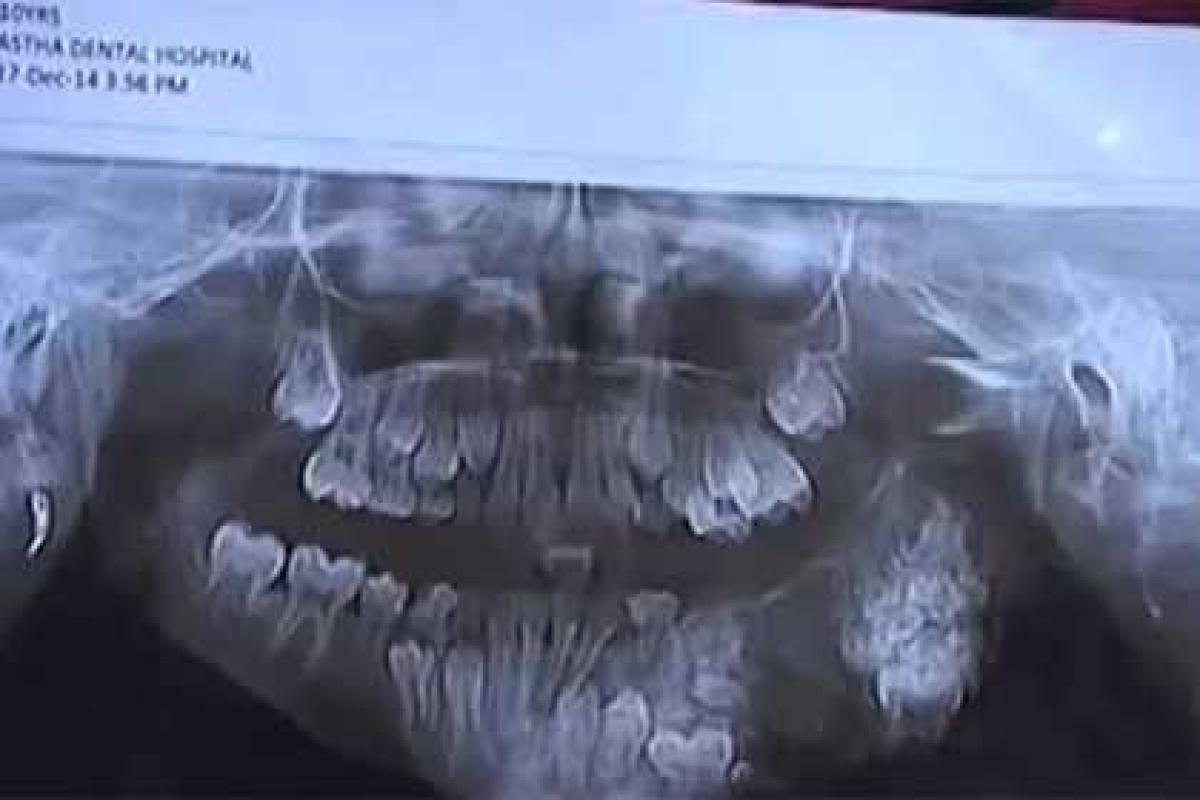

Врачи из индийского города Гвалиор удалили семилетнему мальчику 80 зубов. Об этом сообщает The Times of India. Операция, в которой принимали участие несколько хирургов, продлилась около четырех часов.

У ребенка, чье имя не называется, начался абсцесс верхней челюсти, что очень редко случается в его возрасте. Доктор Анкит Хасгивала, который участвовал в операции, рассказал, что зубы образовывались именно из-за развития абсцесса.

Врач предположил, что если бы родители ребенка не обратились к медикам, за четыре года у мальчика во рту могло бы появиться до двухсот новых зубов. «Хирургия в таких случаях сталкивается с трудностями, потому что челюсть становится слабой и увеличивается риск возникновения переломов», — заявил врач.